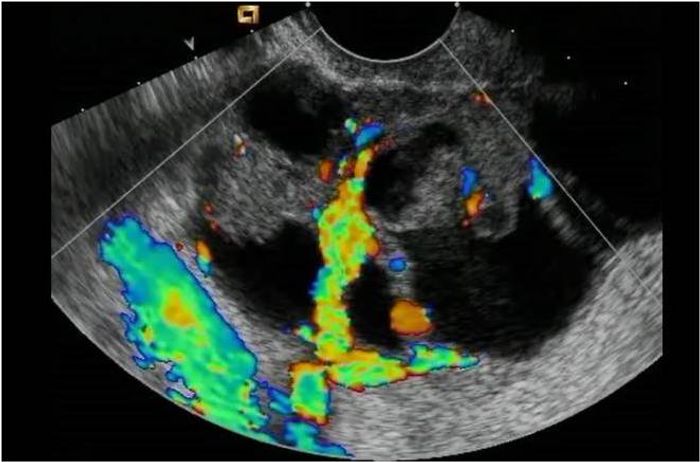

Ovarian Tumors What is the clinical setting when you will consider an ovarian mass? You would consider an ovarian mass, in any woman who comes in complaining of pressure symptoms. These symptoms include urinary frequency, pelvic discomfort, and ...What patients and caregivers need to know about. If you or someone you love has cancer, know what to expect can help you cope. From basic information about cancer and its causes to detailed information about specific types of cancer, including risk factors, early detection, diagnosis and treatment options, you will find it here. More Topics You can help reduce the risk of cancer by making healthy choices like eating well, staying active and not smoking. It is also important to follow recommended screening guidelines, which can help detect certain early cancers. More Topics Cancer Prevention Tools Whether you want to learn about treatment options, get tips on how to deal with side effects, or have questions about health insurance, we are here to help. We can even find a free trip to treatment or a free place to stay when the treatment is away from home. More Top History NAVIGATION WORKING Top Our team of expert journalists brings you all the angles of cancer history – from last-minute news and survivor stories to detailed information about cutting-edge research. More news about Top Story cancer What is needed to overcome cancer? Research. We've invested more than $5 billion in cancer research since 1946, all to find more treatments, discover factors that can cause cancer and improve the quality of life of cancer patients. Life Saving Research Explore Our ResearchWe couldn't do what we do without our volunteers and donors. Together, we are making a difference – and you can too. Become a volunteer, make a deductible tax donation, or participate in a fundraising event to help us save lives. MORE MEASURES TO INVOLVATEOur PassionThe partners highlight the Health Care of the NFLPamperado Chef PartnershipJoin GrowNation The American Cancer Society was unable to do what we do without the support of our partners. Learn more about these partnerships and how you can also join us in our mission to save lives, celebrate lives and lead the struggle for a cancer-free world. Cancer PartnersPartners SpotlightThe NFL Defender Health QuizPampered Chef PartnershipJoin GrowNation At the American Cancer Society, we are on a mission to free the world from cancer. Until we do, we will be funding and conducting research, sharing expert information, supporting patients and spreading the word on prevention. So you can live longer and better. Learn how to use a difference Tests for ovarian cancer If your doctor finds something suspicious during a pelvic exam, or if you have symptoms that may be caused by ovarian cancer, your doctor will recommend tests and tests to find the cause. Medical history and physical exam Your doctor will ask you about your medical history to know possible risk factors, including your family history. You will also be asked if you are having symptoms, when they started, and how long you have had them. Your doctor will likely do a pelvic exam to check if there is an enlarged ovary or signs of fluid in the abdomen (called ascites). If there are reasons to suspect that you have ovarian cancer based on your symptoms and/or physical exam, your doctor will order some tests to check later. Check with a specialist If your pelvic exam or other tests suggest you have ovarian cancer, you will need a doctor or surgeon who specializes in treating women with this type of cancer. A gynecological oncologist is an obstetrician/gynaecologist who is specially trained to treat cancers of the female reproductive system. Treatment by a gynecological oncologist helps ensure that you receive the best type of surgery for your cancer. It has also been shown to help patients with ovarian cancer live longer. Any person suspected of having ovarian cancer should see this type of specialist before being operated. Images Tests Doctors use imaging tests to take pictures of the inside of their body. The imaging tests may show whether a pelvic mass is present, but they cannot confirm that the mass is a cancer. These tests are also useful if your doctor is looking to see if ovarian cancer has spread (metasified) to other tissues and organs. Ultrasound (ultrasonography) uses sound waves to create an image on a video screen. The sound waves are released from a small probe placed in the woman's vagina and a small microphone-like instrument called a sound wave transducer and collects the echoes while bounced organs. A computer turns these echoes into an image on the screen. Ultrasound is often the first test performed if a problem with ovaries is suspected. It can be used to find an ovarian tumor and to check whether it is a solid mass (tumor) or a cyst full of fluid. It can also be used to get a better look at the ovary to see how big it is and how it looks inside. This helps the doctor decide which masses or cysts are more worrying. Computed tomography scans (CT) The X-ray test is a test that makes detailed cross section images of your body. The test can help determine whether ovarian cancer has spread to other organs. CT scans don't show small ovarian tumors well, but they can see larger tumors, and they can be able to see if the tumor is growing in nearby structures. Computed tomography can also find enlarged lymph nodes, signs of cancer spread to the liver or other organs, or signs that an ovarian tumor is affecting your kidneys or bladder. Tomographs are not usually used for biopsy of an ovarian tumor (see biopsy in the "Other Tests") section, but may be used for biopsy of a suspicious metastasis (dissemination area). For this procedure, called TC-guided needle biopsy, the patient remains on the CT scan table, while a radiologist moves a biopsy needle to the mass. CT scans are repeated until doctors trust that the needle is in the dough. A thin sample of needle biopsy (weather fragment) or a sample of nucleus needle biopsy (a thin 1⁄2 inch long tissue cylinder and less than 1/8 inches in diameter) is extracted and examined in the laboratory. Barium enema X-ray A barium enema is a test to see if the cancer has invaded the colon (big instino) or rectum. This test is rarely used for women with ovarian cancer. can be done instead. Magnetic resonance imaging (MRI) also creates cross section images of its interiors. But MRI uses strong magnets to make the images – not X-rays. A contrast material called gadolinium can be injected into a vein before exploration to see the details better. MRI scans are often not used to look for ovarian cancer, but they are particularly useful to examine the brain and spinal cord where cancer may spread. Torax X-ray An analysis can be done to determine whether ovarian cancer has spread (metasified) to the lungs. This spread can cause one or more tumors in the lungs and, more often, causes the fluid to recover around the lungs. This fluid, called pleural effusion, can be seen with chest x-rays and other types of scans. Postitron emission tomography (PET)For a radioactive glucose (sugar) is given to look for cancer. The body cells take different amounts of sugar, depending on how fast they are growing. Cancer cells, which grow rapidly, are more likely to absorb greater amounts of sugar than normal cells. A special camera is used to create an image of radiactivity areas in the body. The image of a PET scanner is not as detailed as a computed tomography or magnetic resonance, but provides useful information about whether abnormal areas seen in these other tests are likely to be cancer or not. If you have already been diagnosed with cancer, your doctor may use this test to see if the cancer has spread to the lymph nodes or other parts of the body. A PET analysis may also be useful if your doctor thinks that the cancer may have spread but does not know where. PET/CT scan: Some machines can make both a PET and a CT scan at the same time. This allows the doctor to compare areas of greater radioactivity in the PET analysis with the most detailed image of that area in the CT analysis. PET scans can help find cancer when it has spread, but are not often used to look for ovarian cancer. Other Laparoscopic Tests This procedure uses a thin, light tube through which a doctor can observe ovaries and other pelvic organs and tissues in the area. The tube is inserted through a small incision (cut) in the lower abdomen and sends the images of the pelvis or abdomen to a video monitor. Laparoscopy provides a vision of organs that can help plan surgery or other treatments and can help doctors confirm (how far the tumor has spread) of the cancer. In addition, doctors can manipulate small instruments through laparoscopic incision to perform biopsies. Colonoscopy A is a way to examine the inside of the large intestine (colon). The doctor looks at the entire length of the colon and rectum with a colonoscope, a thin, flexible and illuminated tube with a small video camera at the end. It is inserted through the anus and in the rectum and colon. Any abnormal area that is veda can be biopsy. This procedure is most commonly used to look for colorectal cancer. Biopsy The only way to determine for sure if a growth is cancer is to remove a piece of it and examine it in the laboratory. This procedure is called a . For ovarian cancer, biopsy is done more commonly by removing the tumor during surgery. In rare cases, a suspected ovary cancer may be biopsied during a laparoscopic procedure or a needle placed directly in the tumor through the skin of the abdomen. The needle will usually be guided by ultrasound or CT scan. This is done only if surgery is not performed due to advanced cancer or other serious medical conditions, as there is concern that a biopsy could spread cancer. If you have ascites (fluid construction within the abdomen), fluid samples may also be used to diagnose cancer. In this procedure, called paracentesis, the skin of the abdomen is numb and a needle attached to a syringe is passed through the abdominal wall to the fluid in the abdominal cavity. Ultrasound can be used to guide the needle. The fluid is absorbed in the syringe and then sent for analysis to see if it contains cancer cells. In all these procedures, the tissue or fluid obtained is sent to the laboratory. There it is examined by a pathologist, a doctor specializing in the diagnosis and classification of diseases by examining cells under a microscope and using other laboratory tests. Blood Tests Your doctor will order blood count tests to make sure you have enough red blood cells, white blood cells and platelets (cells that help stop the bleeding). There will also be tests to measure your kidney and liver function, as well as your overall health. The doctor will also order a CA-125 test. Women who have a high level of CA-125 often refer to a gynecological oncologist, but any woman with suspected ovarian cancer should see a gynecological oncologist, too. Some germ cell cancers can cause high blood levels of tumor markers of human choral gonadotropin (HCG), alpha-fetoprotein (AFP), and/or lactated dehydrogenase (LDH). These may be checked if your doctor suspects that your ovarian tumor may be a germ cell tumor. Some ovarian estromal tumors cause the blood levels of a substance called inhibition and hormones such as estrogen and testosterone to rise. These levels can be checked if your doctor suspects you have this type of tumor. Genetic advice and testing if you have ovarian cancer If you have been diagnosed with epithelial ovarian cancer, your doctor will likely recommend that you receive genetic advice and genetic tests for certain, even if you do not have a family history of cancer. The most common mutations are found in the BRCA1 and BRCA2 genes, but some ovarian cancers are in other genes such as ATM, BRIP1, RAD51C/RAD51D, MSH2, MLH1, MSH6, or PMS6. Genetic testing to search for inherited mutations may be useful in several ways You may have heard of some genetic testing at home. There is concern that these tests will be promoted by companies without giving full information. For example, a test for a small number has been approved by the FDA. However, there are more than 1,000 known BRCA mutations, and those included in the approved test are not the most common. This means that there are many BRCA mutations that would not be detected by this test. A genetic counselor or other qualified medical practitioner can help you understand the risks, benefits, and possible limits of what genetic tests can tell you. This can help you decide whether the test is right for you, and what tests are best. For more information on genetic testing, see Molecular Tests for Gene Changes In some cases of ovarian cancer, doctors may look for specific genetic changes in cancer cells (not blood or saliva samples) that might mean that certain may help treat cancer. These molecular tests can be done in a piece of cancer taken during a biopsy or surgery for ovarian cancer. BRCA1 and BRCA2 genetic mutations: BRCA genes are usually involved in DNA repair and mutations in these genes can keep DNA broken and cells cannot work properly. This can cause cells to grow out of control and become cancer. Some Ovarian cancers have BRCA gene mutations. MSI and MMR Gene Tests: Women who have clear cell, endometrioid or munic ovarian cancer may test their tumor to see if it shows high levels of genetic changes called microsatellite instability (MSI). Tests can also be done to see if cancer cells have changes in any of the desajustment repair genes (MMR) (MLH1, MSH2, MSH6, and PMS2). Changes in MSI or MMR genes (or both) are often seen in people with (HNPCC). Up to 10% of all ovarian epithelial cancers have changes in these genes. There are 2 possible reasons to test ovarian cancers for MSI or for MMR gene changes: NTRK gene mutations: Some ovarian cancers may be tested for changes in one of the NTRK genes. Cells with these genetic changes can lead to abnormal cell growth and cancer. Larotrectinib (Vitrakvi) and entrectinib (Rozlytrek) are targeted drugs that stop proteins made by NTRK abnormal genes. The number of ovarian cancers that have this mutation is very small, but this may be an option for some women. Our team consists of doctors and nurses certified oncology with deep knowledge of cancer care, as well as journalists, editors and translators with extensive medical writing experience. Chen, L., " Berek, J. (2018, January). UpToDate - Ovarian epithelial carcinoma, fallopian tube and peritoneum: clinical characteristics and diagnosis. Consultation on 6 February 2018, from https://www.uptodate.com/contents/epithelial-carcinoma-of-the-ovaryfallopian-tube-and-peritoneum-clinical-features-anddiagnosis.Coleman RL, Liu J, Matsuo K, Thaker PH, Weston SN and Sood Ak. Chapter 86: Carcinoma of the Fallopian Ovaries and Tubes. In: Niederhuber JE, Armitage JO, Doroshow JH, Kastan MB, Tepper JE, eds. Abeloff Clinical Oncology. Philadelphia, Pa. Elsevier: 2020.Konstantinopoulos PA, Norquist B, Lacchetti C, Armstrong D, Grisham RN, Goodfellow PJ, et al. Testing of twin and somatic tumors in epithelial ovarian cancer: ASCO Guideline. J Clin Oncol. 2020. doi: 10.1200/JCO.19.02960. [Epub in front of printing]. Koczkowska M, Zuk M, Gorczynski A, et al. Detection of somatic BRCA1/2 mutations in ovarian cancer - next generation sequencing analysis of 100 cases. Cancer Med. 2016;5(7):1640-1646. Morgan M, Boyd J, Drapkin R, Seiden MV. Ch 89 – Cancers that accumulate in the Ovary. In: Abeloff MD, Armitage JO, Lichter AS, Niederhuber JE, Kastan MB, McKenna WG,eds. Clinical oncology. 5th edition. Philadelphia, PA: Elsevier; 2014: 1592.National Integral Cancer Network (NCCN)—Genetic/Familial High Risk Assessment: Breast, Ovarian and Pancreatic. V1.2020. Access March 26, 2020 from https://www.nccn.org/professionals/physician_gls/pdf/genetics_bop.pdf Comprehensive Cancer Network (NNCN) - Ovarian Cancer including Autumn Tube and Primary Peritoneal Cancer. (2018, February 2). On February 5, 2018, from https://www.nccn.org/professionals/physician_gls/pdf/ovarian.pdf Comprehensive Cancer Network (NCCN) - Ovarian Cancer including Otope Tube Cancer and Primary Peritoneal Cancer. V1.2020. Access March 26, 2020 from http://www.nccn.org/professionals/physician_ gls/pdf/ovarian pdfOkamura R, Boichard A, Kato S, Sicklick JK, Bazhenova L, Kurzrock R. Analysis of NTRK Alterations in Malignities Pan-Cancer Adult and Pediatrics: Implications for NTR JCO Precis Oncol. 2018;2018:10.1200/PO.18.00183. doi:10.1200/PO.18.00183 Tewari KS, Penson RT and Monk BJ. Chapter 77: Ovarian Cancer. In: DeVita VT, Lawrence TS, Rosenberg SA, eds. DeVita, Hellman and Rosenberg Cancer: Principles " Oncology Practice. 11th edition. Philadelphia, Pa: Lippincott Williams " Wilkins; 2019.Weber S, McCann CK, Boruta DM, Schorge JO, Growdon WB. Laparoscopic Surgical staging of premature ovarian cancer. Reviews in Obstetrics and Gynaecology. 2011;4(3-4):117-122.Chen, L., & Berek, J. (2018, January). UpToDate - Ovarian epithelial carcinoma, fallopian tube and peritoneum: clinical characteristics and diagnosis. Consultation on 6 February 2018, from https://www.uptodate.com/contents/epithelial-carcinoma-of-the-ovaryfallopian-tube-and-peritoneum-clinical-features-anddiagnosis.Coleman RL, Liu J, Matsuo K, Thaker PH, Weston SN and Sood Ak. Chapter 86: Carcinoma of the Fallopian Ovaries and Tubes. In: Niederhuber JE, Armitage JO, Doroshow JH, Kastan MB, Tepper JE, eds. Abeloff Clinical Oncology. Philadelphia, Pa. Elsevier: 2020.Konstantinopoulos PA, Norquist B, Lacchetti C, Armstrong D, Grisham RN, Goodfellow PJ, et al. Testing of twin and somatic tumors in epithelial ovarian cancer: ASCO Guideline. J Clin Oncol. 2020. doi: 10.1200/JCO.19.02960. [Epub in front of printing]. Koczkowska M, Zuk M, Gorczynski A, et al. Detection of somatic BRCA1/2 mutations in ovarian cancer - next generation sequencing analysis of 100 cases. Cancer Med. 2016;5(7):1640-1646. Morgan M, Boyd J, Drapkin R, Seiden MV. Ch 89 – Cancers that accumulate in the Ovary. In: Abeloff MD, Armitage JO, Lichter AS, Niederhuber JE, Kastan MB, McKenna WG,eds. Clinical oncology. 5th edition. Philadelphia, PA: Elsevier; 2014: 1592.National Integral Cancer Network (NCCN)—Genetic/Familial High Risk Assessment: Breast, Ovarian and Pancreatic. V1.2020. Access March 26, 2020 from https://www.nccn.org/professionals/physician_gls/pdf/genetics_bop.pdf Comprehensive Cancer Network (NNCN) - Ovarian Cancer including Autumn Tube and Primary Peritoneal Cancer. (2018, February 2). On February 5, 2018, from https://www.nccn.org/professionals/physician_gls/pdf/ovarian.pdf Comprehensive Cancer Network (NCCN) - Ovarian Cancer including Otope Tube Cancer and Primary Peritoneal Cancer. V1.2020. Access March 26, 2020 from http://www.nccn.org/professionals/physician_ gls/pdf/ovarian pdfOkamura R, Boichard A, Kato S, Sicklick JK, Bazhenova L, Kurzrock R. Analysis of NTRK Alterations in Malignities Pan-Cancer Adult and Pediatrics: Implications for NTR JCO Precis Oncol. 2018;2018:10.1200/PO.18.00183. doi:10.1200/PO.18.00183 Tewari KS, Penson RT and Monk BJ. Chapter 77: Ovarian Cancer. In: DeVita VT, Lawrence TS, Rosenberg SA, eds. DeVita, Hellman and Rosenberg Cancer: Principles " Oncology Practice. 11th edition. Philadelphia, Pa: Lippincott Williams " Wilkins; 2019.Weber S, McCann CK, Boruta DM, Schorge JO, Growdon WB. Laparoscopic Surgical staging of premature ovarian cancer. Reviews in Obstetrics and Gynaecology. 2011;4(3-4):117-122. Last revision: April 3, 2020 American Cancer Society medical information is copyright material. For reprint requests, please see our . More In ovarian cancer Imagine a world free of cancer. Helps make it a reality. Cancer Information Programs & ServicesAbout ACSMore ACS SitesFollow us Cancer, Response, and Hope Information. Available every minute of every day. Follow Us© 2021 American Cancer Society, Inc. All rights reserved. The American Cancer Society is an organization exempted from qualified tax 501(c)(3). Tax identification number: 13-1788491. Cancer.org is a courtesy of the Leo family and Gloria Rosen. Select a Hope Lodge